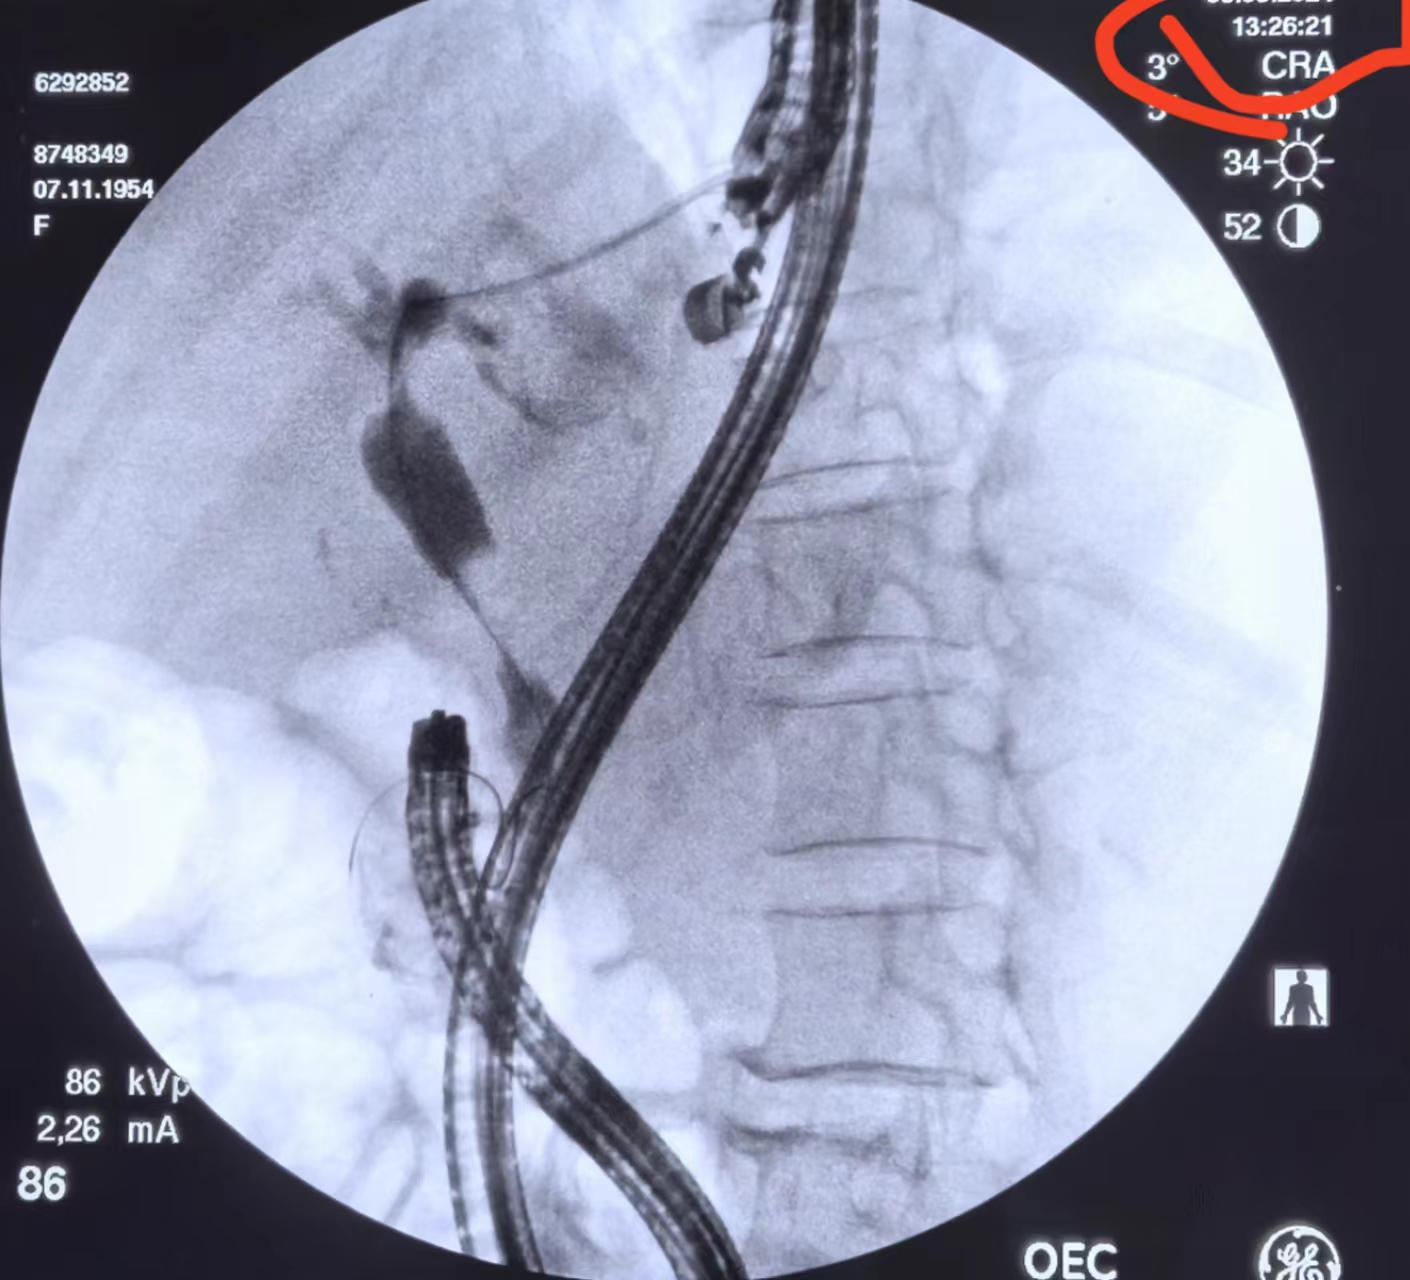

导丝越过肝门狭窄段后再越过胆总管狭窄段

但是导丝出十二指肠乳头的时候花了点时间

大概十五分钟之后导丝进入十二指肠,计划进行会师